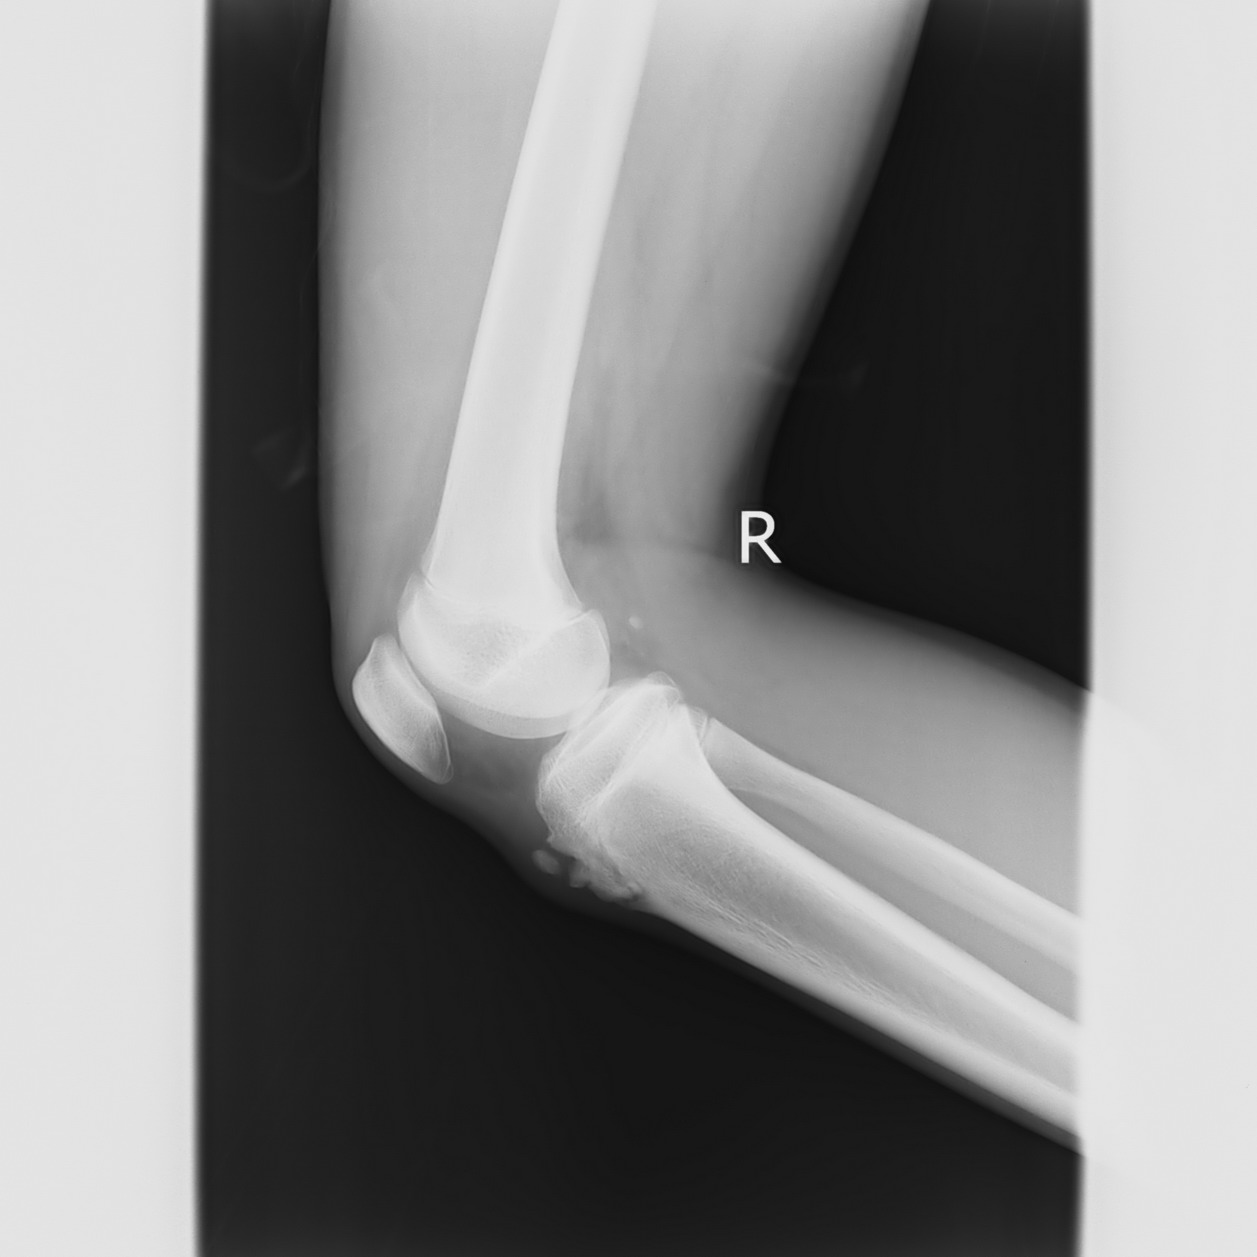

以下是引用qc80012345在2008-5-3 18:26:00的发言:[br]胫前结节缺血性骨软骨炎。

以下是引用宇宙ct在2008-5-3 19:16:00的发言:[br]胫前结节缺血性骨软骨炎